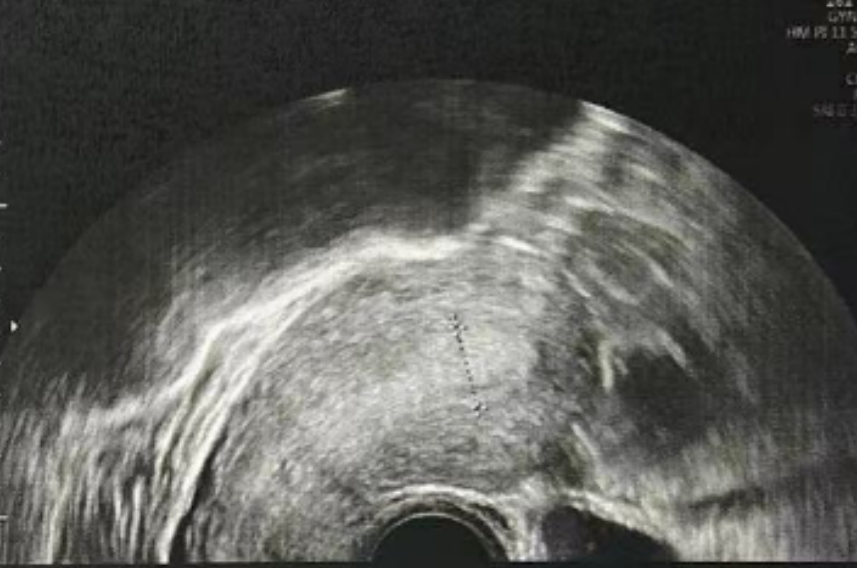

子宫内膜厚度:4.6 毫米,子宫有瘢痕大小 0.76*0.19 厘米

雌二醇:241 pg/mL

孕酮:0.13 ng/ml

子宫内膜厚度:9.3-10 毫米

- 有粘液滞留在腔内,从峡部瘢痕延伸至子宫底

- 双卵巢无囊肿

- 计划在胚胎移植前重复超声检查以冲洗峡部瘢痕

雌二醇:210.52 pg/mL

孕酮:0.3 ng/ml

子宫内膜厚度:8.9 毫米

微创清积液

在进行3毫升的子宫峡部切口冲洗后,经过经腹超声检查显示子宫内膜呈三线状,且子宫腔内未见液体。

• Pre-Irrigation灌洗前: